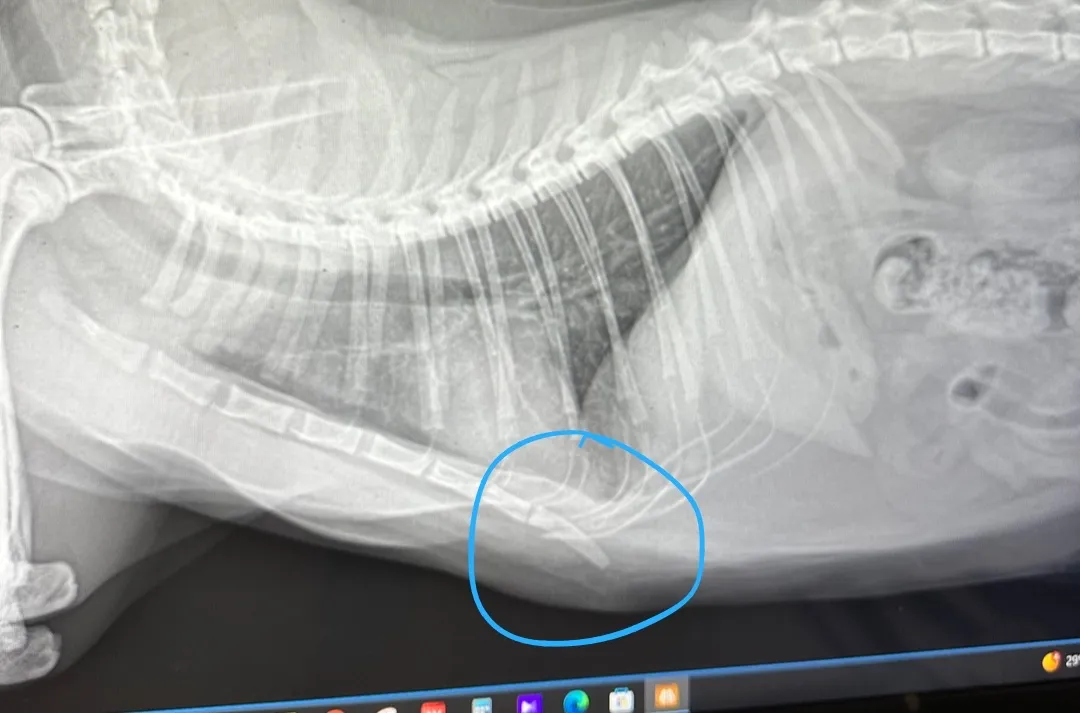

고양이 엑스레이

아이가 선반 올라가다가 떨어지고나서 평소랑 달라서 병원에 가서 엑스레이 찍엇는데 문제는 없다고 하셨는데 다른고양이들이랑 다르게 뼈가 내려가??있다고 하시더라구요 뼈가 저렇게 있어도 아이한테 문제가 안 생기나요??

1번째 파일